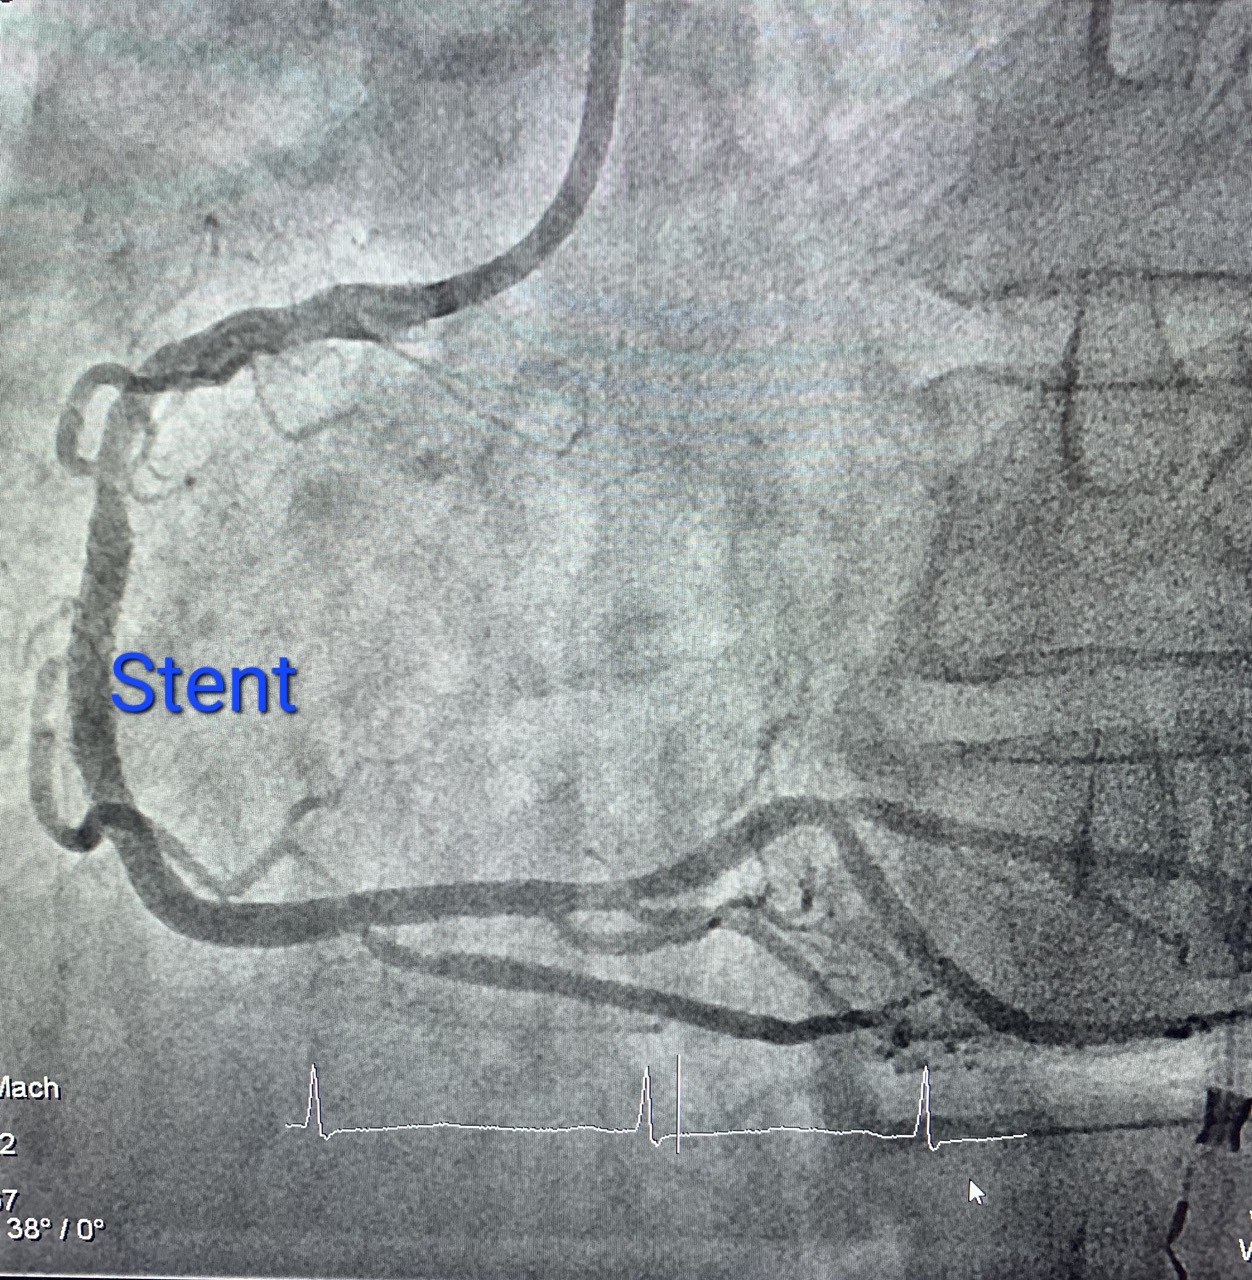

Gần đây, bệnh nhân cảm giác đau giữa xương ức kiểu bóp nghẹt kèm tê nhẹ hàm. Bệnh nhân sau đó đi khám được các bác sĩ chuyên khoa tim mạch chẩn đoán đau ngực do bệnh lý mạch vành và được chỉ định nhập viện chụp mạch vành. Kết quả sau chụp mạch vành cho thấy bệnh nhân bị hẹp 95% động mạch vành phải. Sau khi được các bác sĩ can thiệp đặt stent vành phải các triệu chứng đau ngực của bệnh nhân đã cải thiện rõ rệt.

Hình ảnh trước can thiệp và sau can thiệp. Ảnh BS cung cấp